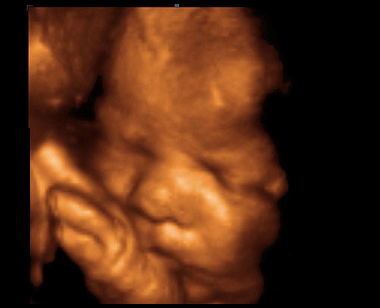

Zhruba nejpozději do konce prvního trimestru žena obdrží těhotenskou průkazku. Jedná se o nejdůležitější dokument v těhotenství, který by žena měla mít stále u sebe. Do schématu jednotlivých návštěv v těhotenské poradně, která mají v počátku interval 4-6 týdnů, jsou zahrnuta i tři ultrazvuková vyšetření. První v 11. až 13. týdnu těhotenství, sloužící k určení termínu porodu dle velikosti plodu, ale i vývojových vad plodu. Druhé ve 20. až 22. týdnu těhotenství, které je zaměřeno na velikost plodu, určení množství plodové vody, uložení placenty, pohybů plodu a také vývojových vad. Obdobně pak třetí ultrazvuk mezi 30. až 32. týdnem těhotenství.

Ultrazvuk

V průběhu těhotenství se provádí ultrazvuková vyšetření za účelem screeningu vývojových vad. Kdy jednotlivá vyšetření probíhají a co znamenají zkratky...